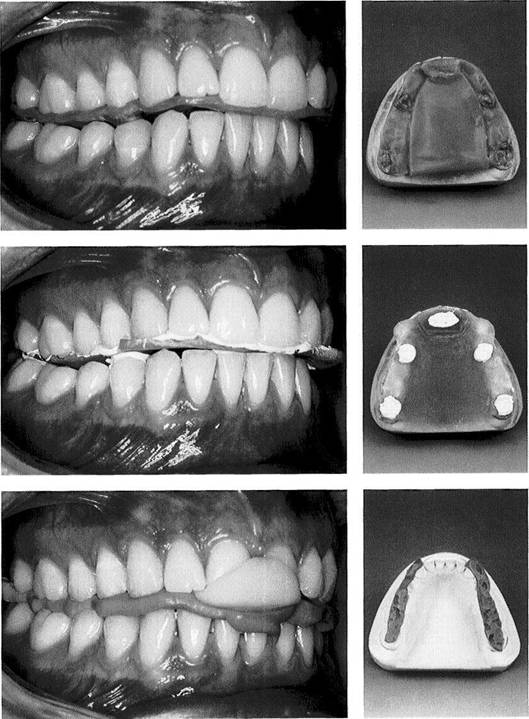

Wax occlusion record

A "classic" occlusion record of Beauty-Pink-Wax corrected with Aluwax against the lower teeth.

Right: The wax record base is rein­forced with an additional layer of wax on both the superior and inferi­or surfaces of the palatal area. An anterior buildup of wax provides for disclusion of the posterior teeth. Refinement is accomplished by adding Aluwax to the premolar and molar areas to form occlusal stops.

Synthetic resin occlusion record

Record bases made of light-curing resin offer the advantage of dimen­sional stability. They can readily be trimmed back to minimize interfer­ence with the occlusion if neces­sary.

Right: A resin record base on the maxillary cast after occlusal refine­ment. The anterior bite plane paral­lel with the occlusal plane helped to avoid posterior tooth contact with the record base.

Silicone occlusion record

Whenever silicone or plaster is to be used to register the centric jaw rela­tion, an anterior bite index of cold-curing resin should first be formed to prevent occlusion of the posteri­or teeth.

Right: The silicone record is judi­ciously trimmed back with a scalpel and placed to fit precisely on the mandibular cast.

One advantage of this registration technique is that there is virtually no impingement upon the tongue space.